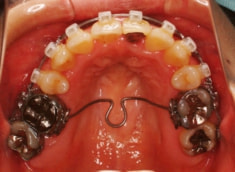

治療開始時

治療開始から約1年後